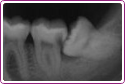

Ząb Pana Andrzeja wymagał leczenia kanałowego. Kanały były zakrzywione. Na zdjęciu efekt 30 min pracy.